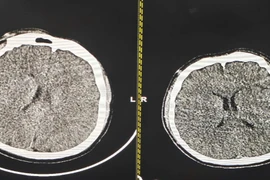

Phù não ở bệnh nhân sống sót sau treo cổ tự tử, là một biến chứng nghiêm trọng đe dọa tính mạng. Kiểm soát thân nhiệt chỉ huy là phương pháp hồi sức quan trọng giúp bảo vệ não và cải thiện kết quả điều trị.